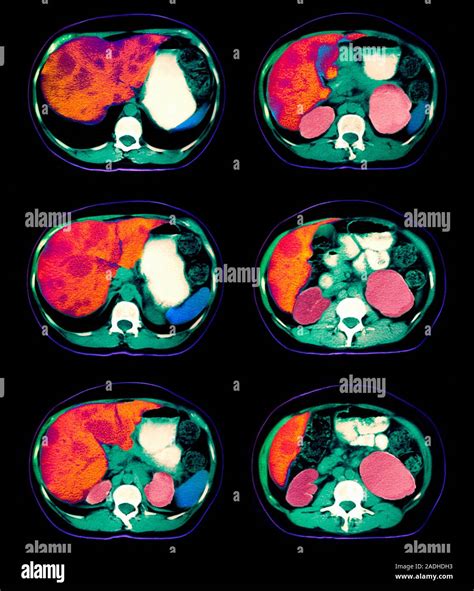

CT Scan Provides detailed cross-sectional images of the abdomen.

MRI Offers highly detailed imagery of soft tissues within the liver.